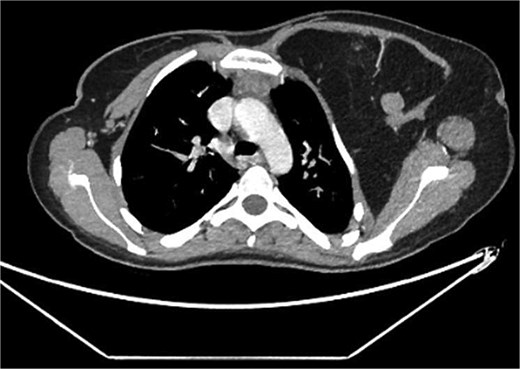

A 22-year-old female presented with progressive swelling in the left anterior chest wall above the left breast, associated with needle-like chest pain, left upper limb tingling, and weakness. The patient had a history of childhood cystic hygroma in the left axilla, previously excised. She denied constitutional symptoms but reported compressive symptoms such as shortness of breath, dysphagia, and hoarseness. A family history of breast cancer with thyroid metastasis was noted in her mother. On examination, the patient exhibited multiple bilateral solitary thyroid nodules and a bulky swelling in the left anterior chest and axilla. Computed tomography (CT) imaging (Fig. 1) revealed hypodense bilateral thyroid nodules, with magnetic resonance imaging (MRI) (Fig. 2) showing an enhancing left axillary lesion (2 cm, previously 1 cm) and an anterior chest wall lesion (1 cm). The mass, measuring 23 × 8 cm, extended to the lower left neck, left chest wall, and left axilla, encasing the neurovascular bundle without muscle or osseous invasion (Fig. 3). Fine-needle aspiration (FNA) cytology (Fig. 4) of the right thyroid nodule indicated atypia of undetermined significance (Bethesda III), while left-sided nodules and biopsies from the axilla, breast, and neck confirmed benign mature adipose tissue. The patient underwent total thyroidectomy, level V left neck exploration, and excision of lipomatous masses from the axilla, anterior chest, and breast, involving multiple surgical teams. Intraoperatively, vocal cords were preserved, and clear planes for lipoma excision were identified. The total excised lipomatous tissue weighed 13.57 kg (Fig. 5). Pathological examination confirmed mature adipose proliferation with no malignancy. Fluorescence in situ hybridization (FISH) ruled out MDM2 amplification, and genetic testing returned negative. Postoperatively, the patient developed deep vein thrombosis (DVT) in the left upper limb, diagnosed via Doppler study, and was treated with low-molecular-weight heparin (LMWH) followed by rivaroxaban. Follow-up MRI at 2 days and 3 months confirmed no residual or recurrent tissue growth. The patient started levothyroxine for thyroid function management and monitored for optimal dosing.

Interval increase in size of the large left upper lateral cervical, sub-pectoral, and axillary region fatty lesion protruding beyond the pectoralis major muscle into the upper breast region, keeping with lipomatosis.

Left chest wall lipomatosis with extension to the left neck and left axilla with thin septations, and there is a small enhancing focus (within the fatty lesion) which could be a small enhancing nodule or lymph node. The overall measurement has relatively increased (consider patient maturation).